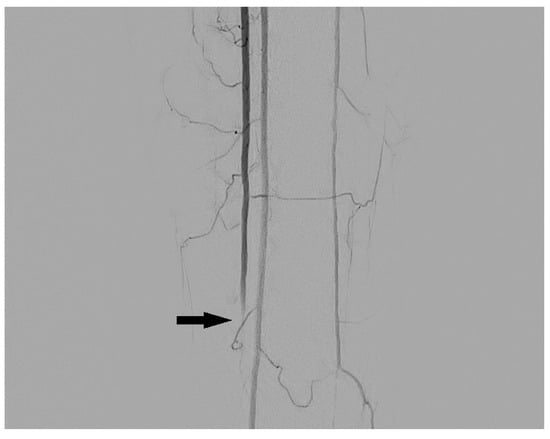

3.1. Stenosis and Occlusion

3.2. Dissection